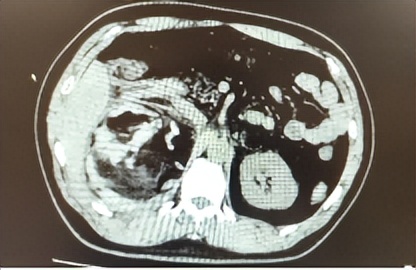

阳光讯(记者 郑亚雷 通讯员 周海彬)近日,40岁的王先生(化名)因“右侧腹部剧烈疼痛3小时”紧急前往西安医学院第一附属医院急诊科就诊。急诊CT检查显示:右侧肾上腺区存在巨大占位性病变,直径约10厘米,疑似肿瘤破裂合并出血。病情危急,急诊科立即联系泌尿外科会诊。

西安医学院第一附属医院泌尿外科宋益挺副主任医师迅速到场,结合影像资料与实验室检查结果,初步判断患者为肾上腺肿瘤自发性破裂出血。在科主任张鸿毅的指导下,团队立即启动急诊收治流程,将患者快速转入泌尿外科病房。